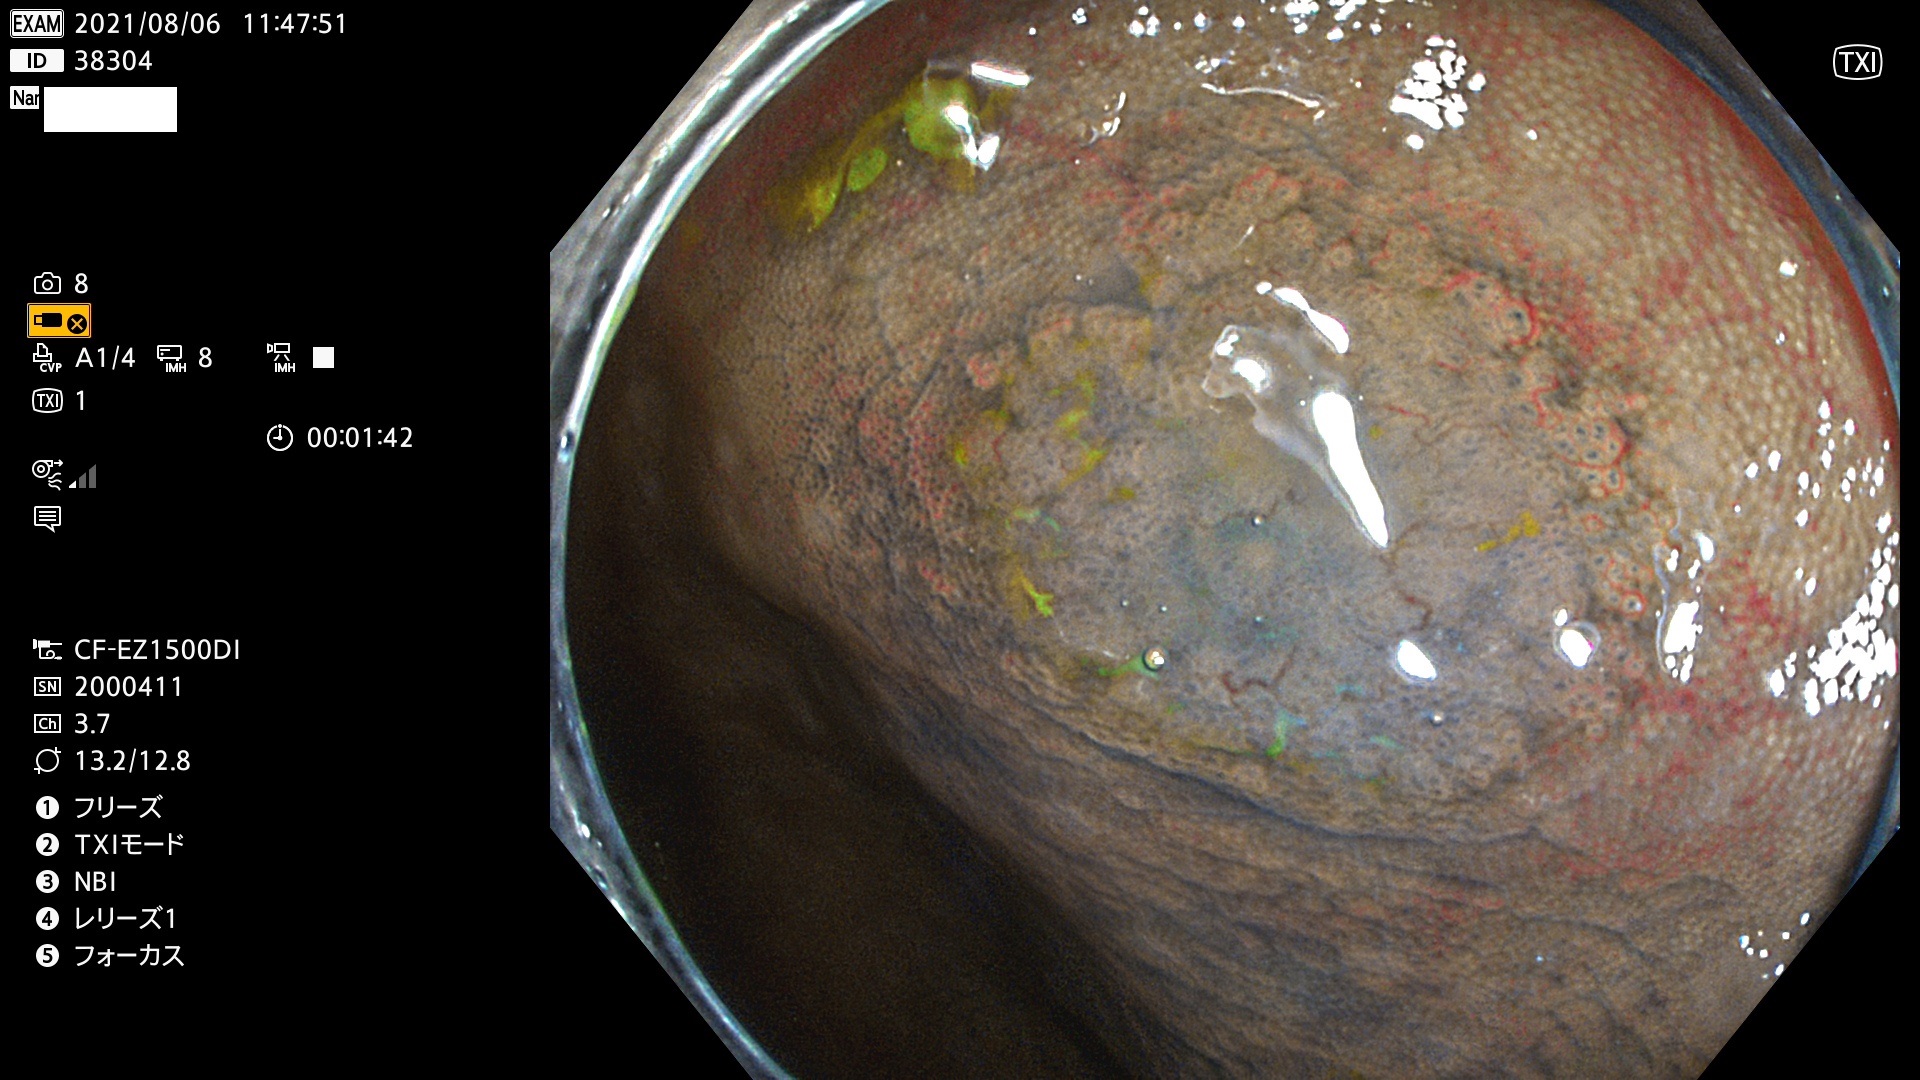

38300 38301 38302 38303 38304 38306 38307 38308 38309 38310 38311 38312 38313 38314 38315 38316 38317 38319 38321 38322 38323 38324 38325 38327 38331 38332 38333 38334 38337 38338 38339 38340 38341 38343 38346 38348 38349 38350 38351 38352 38353 38354 38355 38358 38359 38360 38361 38362 38363 38365 38366(SSAP) 38368 38369 38370 38371(SSAP) 38372 38374 38375 38376 38377 38378 38380 38381 38382 38383 38384 38385 38386 38388 38389 38391(SSAP) 38395 38397 38399

発見困難で危険性の高い平坦型病変(上記100名より抽出)